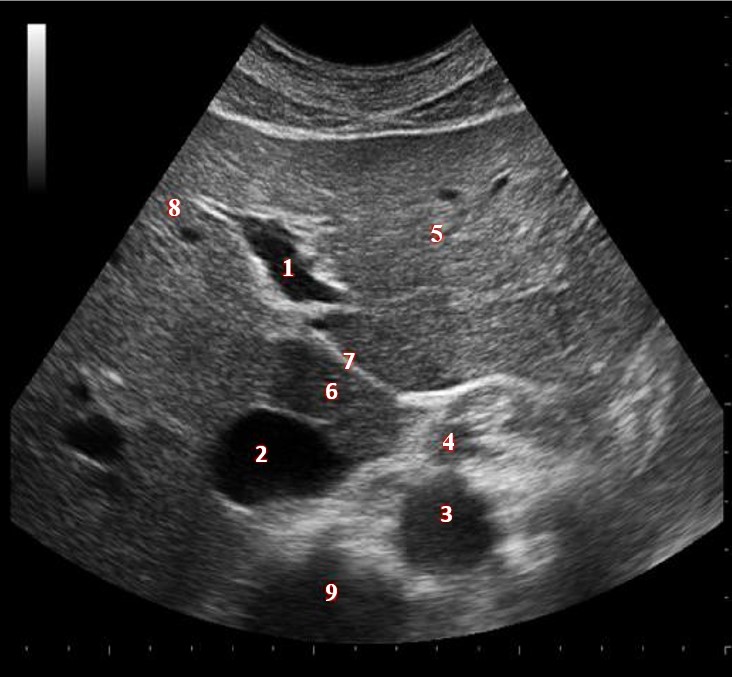

Which of the following structures is labeled #5?

What lobe of the liver is indicated by #1?

What structure/vessel is indicated by #8?

What lobe of the liver is indicated by #2?

Which of the following structures is labeled #1?

Which of the following structures is labeled #7?

Which of the following structures is labeled #2?

What structure/vessel is indicated by #9?

What structure/vessel is indicated by #4?

What structure/vessel is indicated by #4?

What structure/vessel is indicated by #2?

Which of the following structures is labeled #6?

Which of the following structures is labeled #3?

What structure/vessel is indicated by #2?

What structure/vessel is indicated by #6?

What structure/vessel is indicated by #7?

Which of the following structures is labeled #8?

Which of the following structures is labeled #2?

What structure/vessel is indicated by #3?